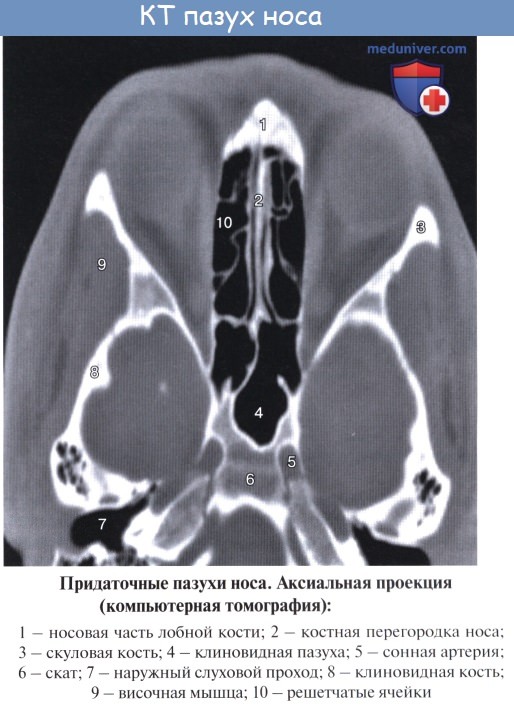

Клиновидная пазуха, sinus sphenoidalis, расположена в теле клиновидной кости непосредственно позади решетчатого лабиринта над хоанами и сводом носоглотки. Сагиттально расположенной перегородкой пазуха делится на две в большинстве случаев неодинаковые по объему части. На передней, наиболее тонкой, стенке в каждой половине пазухи находится отверстие, apertura sinus sphenoidalis. Форма и размеры клиновидной пазухи сильно варьируют. Ее верхняя стенка обращена к передней и средней черепным ямкам.

Средний отдел верхней стенки клиновидной пазухи соответствует турецкому седлу с расположенным в его ямке гипофизом, а кпереди от них — перекресту зрительных нервов.

Снаружи по боковой стенке клиновидной пазухи проходят внутренняя сонная артерия и пещеристый венозный синус. Кроме того, по бокам пазухи проходят глазодвигательный, блоковый и отводящий нервы, прободающие наружную стенку пешеристого синуса, а также I ветвь тройничного нерва.

Нижняя стенка клиновидной пазухи образует свод полости носа.

Кровоснабжение околоносовых пазух происходит из ветвей внутренней и наружной сонных артерий, главным образом через глазную и верхнечелюстные артерии. Вены гайморовой пазухи анастомозируют с венами лица и крыловидного сплетения, а вены лобной пазухи — с венами твердой мозговой оболочки, с продольным синусом и пещеристым синусом. По этим путям иногда проникает инфекция в глазницу или полость черепа.